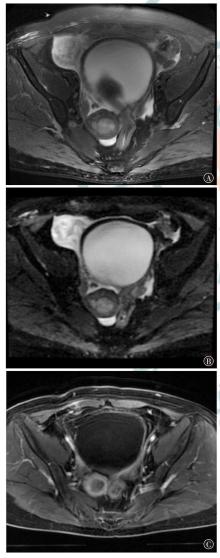

Watanabe Y, Matsunuma K, Kaneda T. A case of successful anesthetic management in a patient with trousseau's syndrome who underwent surgery for malignant ovarian tumor[J]. JA Clin Rep, 2020, 6(1): 32. DOI: 10.1186/s40981-020-00339-2.